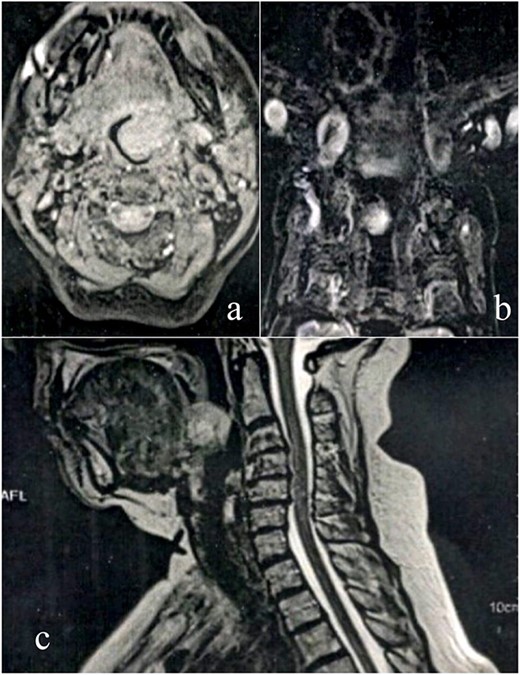

A female patient, 72 years old, sought care reporting intermittent dysphonia for 5 months. She claimed to have hypothyroidism and hypertension, using continuous medication. She denied other symptoms such as weight loss, dyspnea, dysphagia and fever. Two external laryngoscopies had been performed, and a vegetating lesion was found on the left lateral wall of the oropharynx, measuring 3.5 × 2.5 cm with mass effect merging with the left palatine tonsil (Fig. 1). Nuclear magnetic resonance revealed a mixed lesion, containing a cyst with a thick content measuring 23 × 22 × 24 mm (Fig. 2). Given this finding, the chosen procedure was resection by suspension laryngoscopy with the use of CO2 laser. Mass resection of the left tonsil was performed successfully and uneventfully, removing a solid, fibroelastic, 3 × 2 cm mass. Laryngoscopy after 1 month showed good healing, with no evidence of remaining lesions. After histopathological analysis, the tumor was benign and well-delimited (Fig. 3). The main diagnostic hypothesis was myoepithelioma of the oropharynx; however, after analysis of the immunohistochemical evaluation of the specimen, the result was inconclusive between myoepithelioma or PA, favoring the second.

(a) Epithelioid area on the left. (b) Area of triple epithelial cell phenotype (plasmacytoid, myoepithelial and ductal). (c) Highly cellular lesion with a tendency to cellular monomorphism and scarce stromal component. (d) Very limited neoplasm—green India ink—margin surgical HE, ×40.

PA is commonly represented by having wide architectural and cytomorphological diversity. It has cells capable of differentiating into epithelium and myoepithelium, as well as into mesenchymal cells of the chondroid, myxoid and even bone types. The epithelial cells, arranged in an arrangement of cords or leaflets, can be ductal or non-ductal, and the presentation can be predominant with epithelial richness or have only foci of epithelium, thus being variable [7].

Regarding the differentiation between myoepithelioma and PA, the analysis of the presence of ducts is a plausible way of distinguishing since these are rare in myoepitheliomas. Although less frequent, myoepithelioma may present myxoid or chondroid stroma, which bears a resemblance to PA. Some other common findings may make the diagnosis difficult, such as the abundance of myoepithelium and areas with pure myoepithelial cells [5, 8].

The positivity of markers such as p63, myoepithelial cell markers and AE1/AE3, epithelial cells, found in immunohistochemistry (Fig. 4) may also be present in myoepitheliomas but in a lower percentage, ranging from 17 and 44% [8]. However, in this report, a large number of plasmacytoid epithelial cells and mainly ductal formations are superimposable characteristics of the PA, despite the scarce stromal component and foci of myoepithelium.